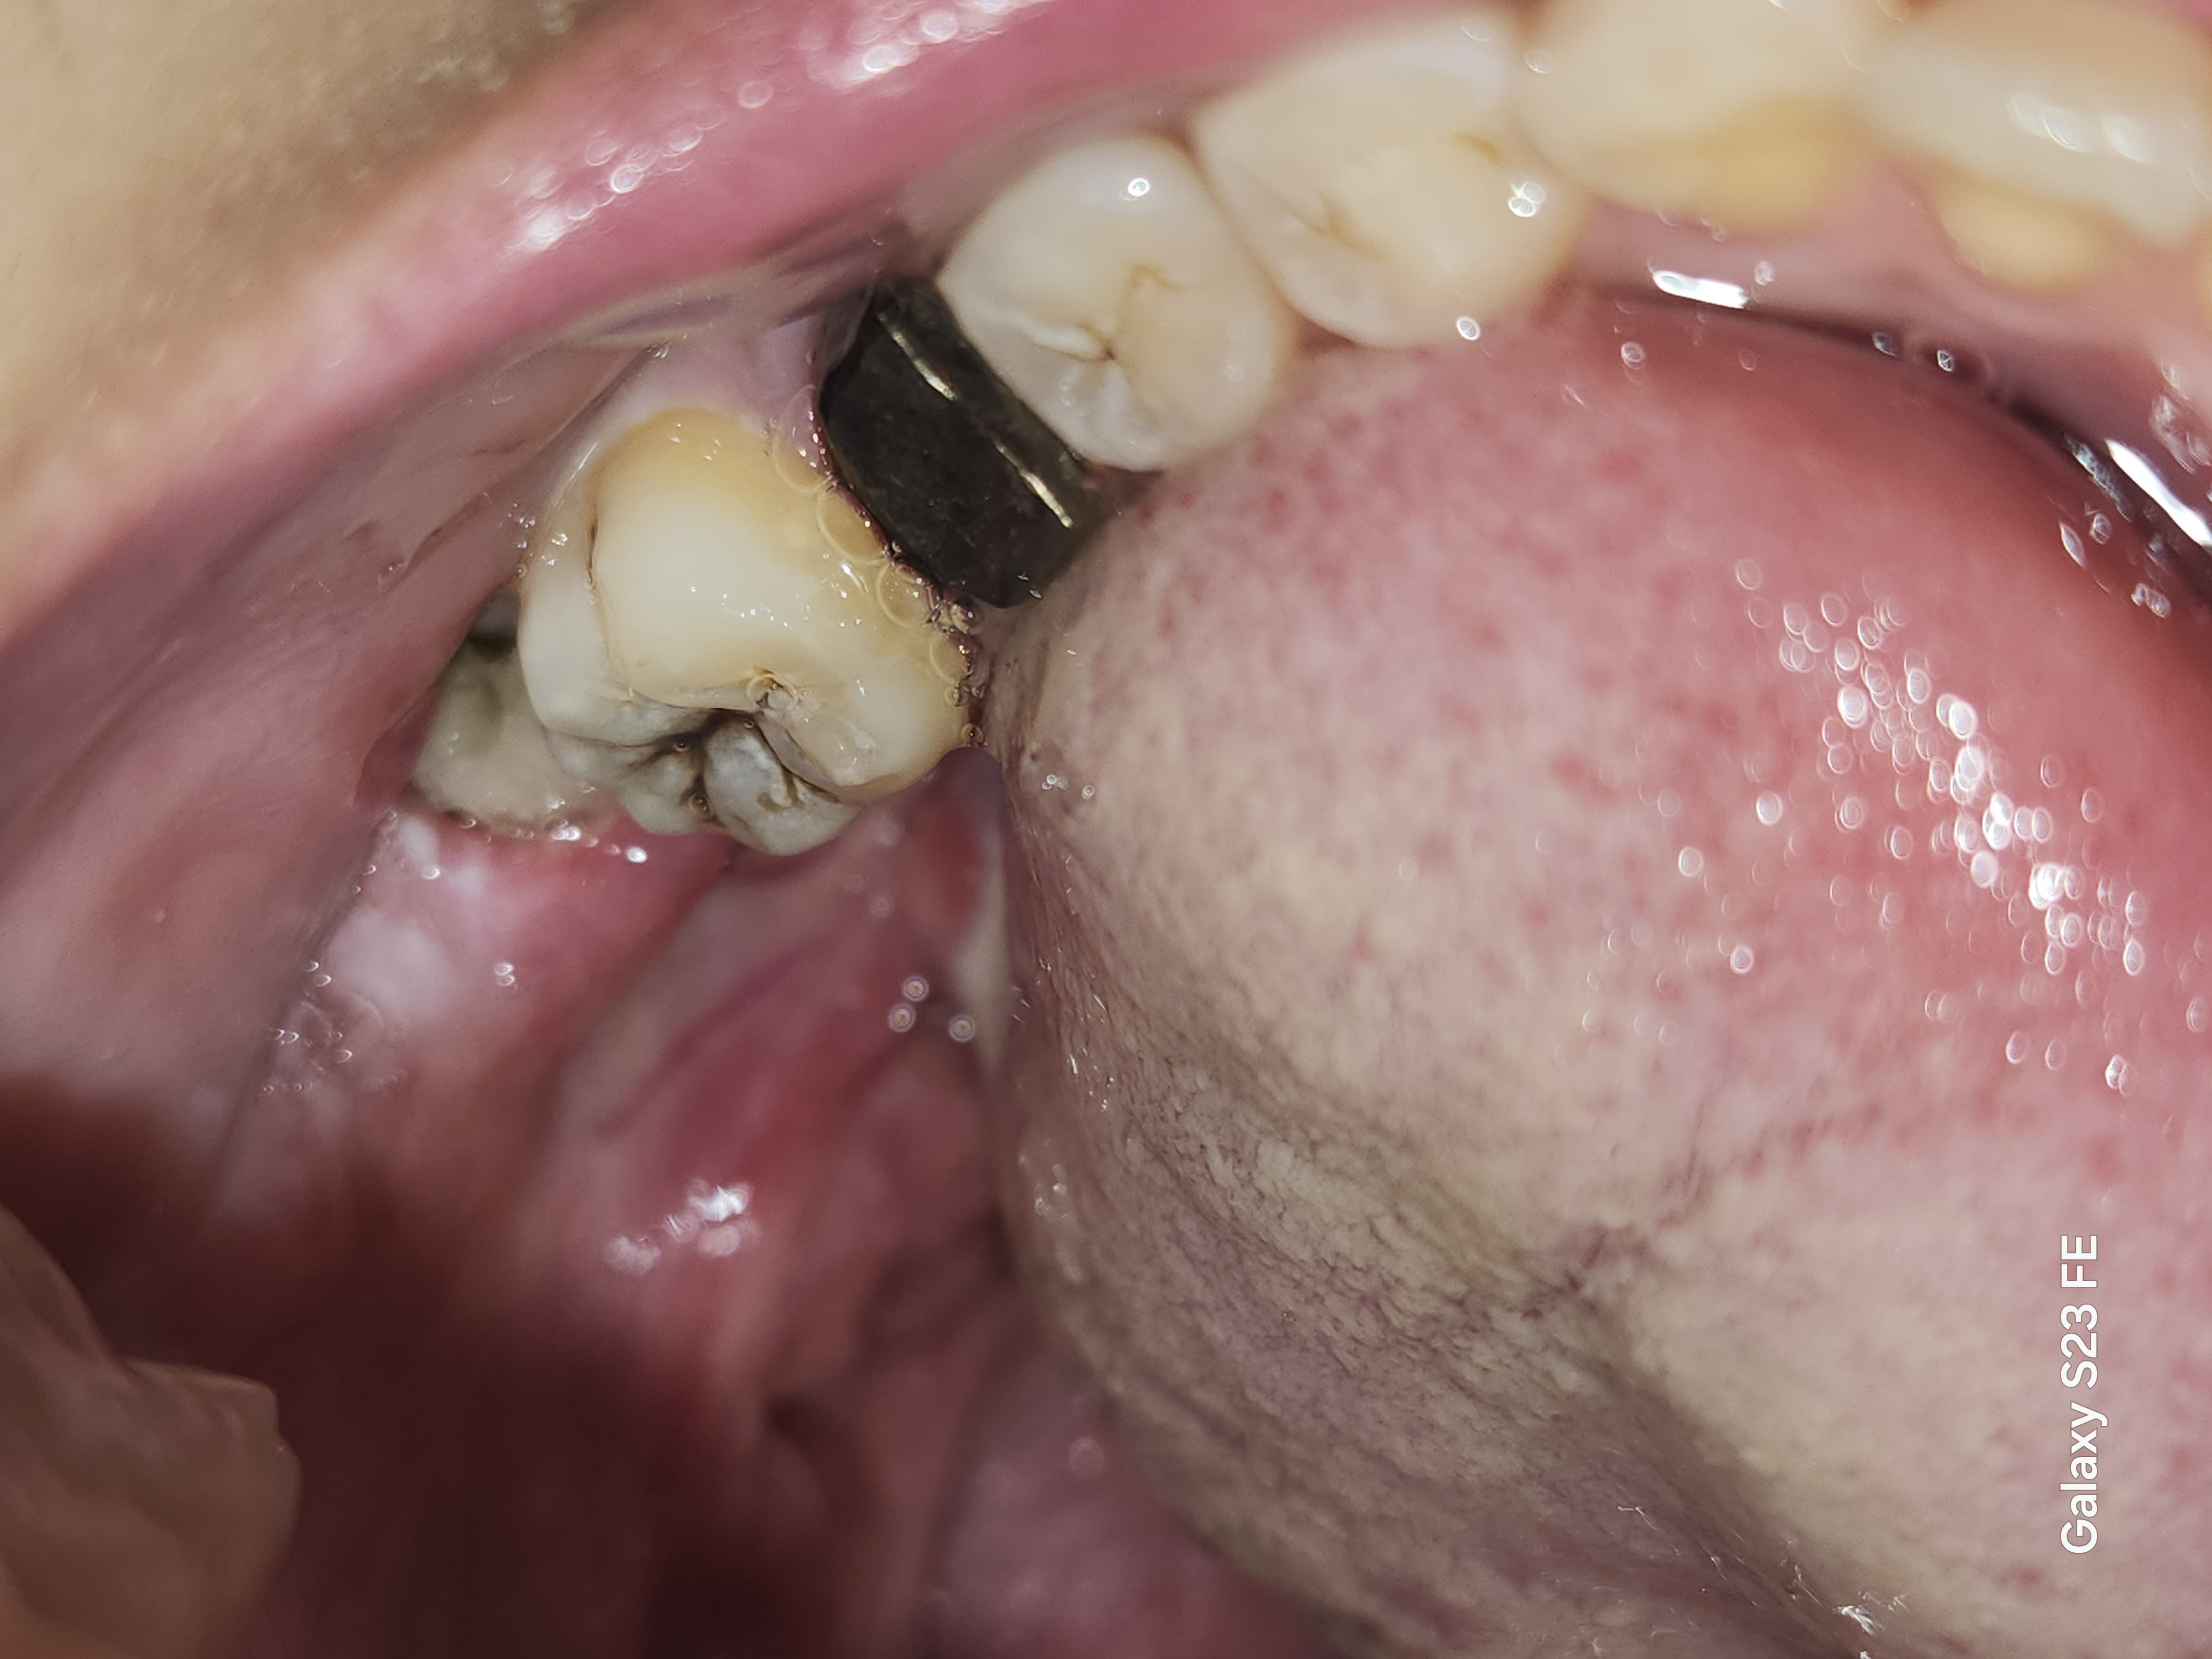

親知らず抜歯後、4日経っても痛みが酷く、ドライソケットではないかと不安です。